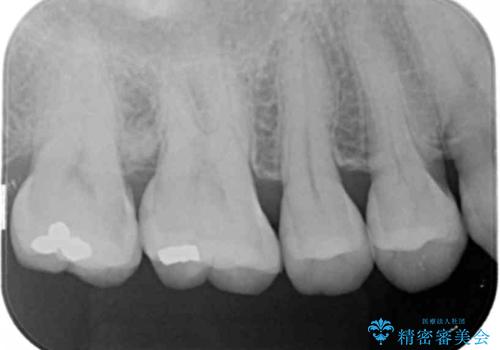

- 定期検診にて来院、症状はないものの右上の奥歯に虫歯が再発していました。

視診・レントゲン画像より虫歯の大きさを判断し、虫歯の除去後セラミックインレーにて修復することになりました。